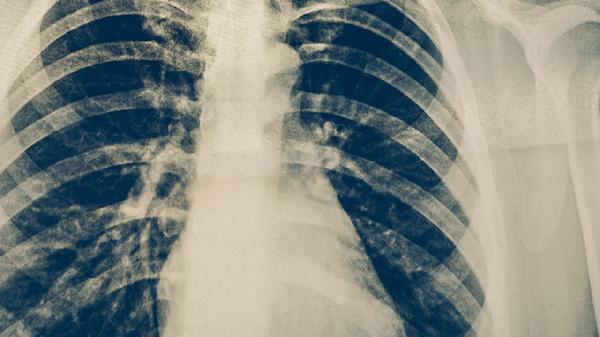

耐多药肺结核可以诊治,但治疗难度较大且周期较长,需在专业医疗机构进行规范化治疗。耐多药肺结核是指对异烟肼和利福平两种一线抗结核药物同时耐药的结核病,治疗需根据药敏试验结果制定个体化方案。

耐多药肺结核患者应保持充足营养摄入,每日蛋白质供给量需达到每公斤体重1.2-1.5克。饮食宜选用鸡蛋、鱼肉、瘦肉等优质蛋白,配合新鲜蔬菜水果补充维生素。避免吸烟饮酒,保持规律作息,居住环境需通风良好。治疗期间须严格隔离,痰液需消毒处理,密切接触者应进行结核病筛查。建议每2-3个月复查胸部CT,完成治疗后仍需随访2年以监测复发。